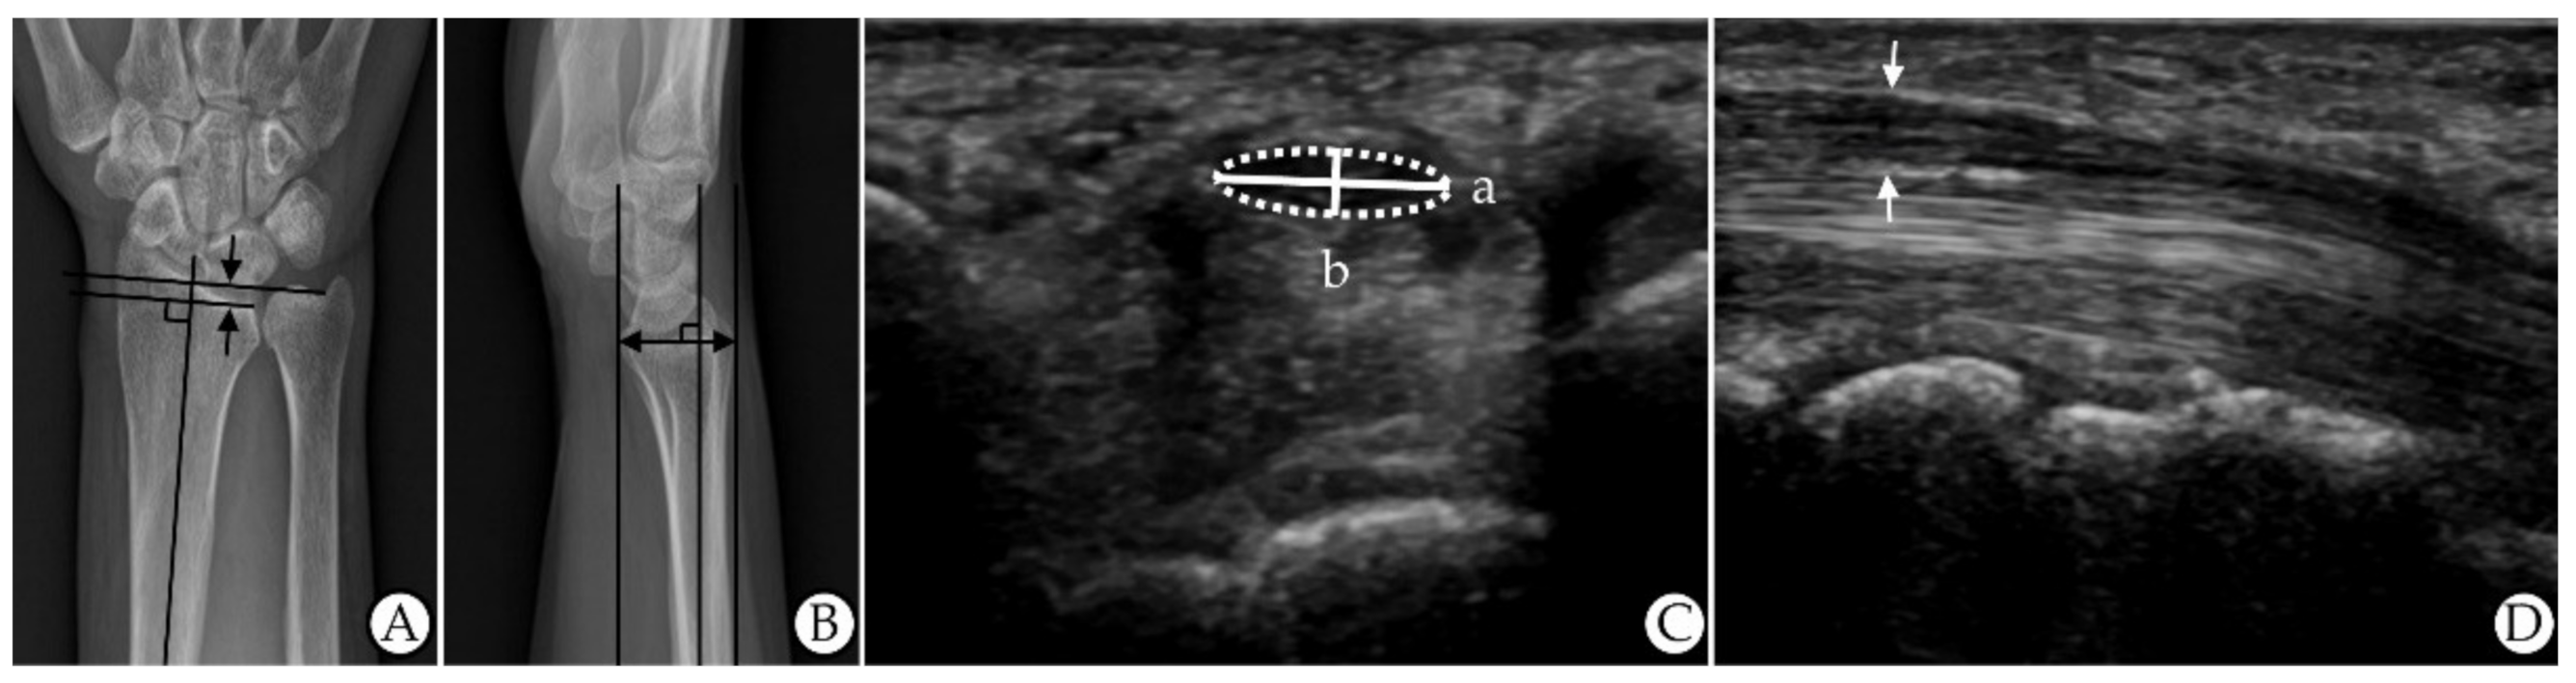

All patients underwent simple X-rays of the posteroanterior and lateral view of the wrist. To obtain the posteroanterior view, the elbow was flexed 90°, the forearm was pronated, and the wrist was in a neutral position. The UV was defined as the distance between horizontal lines (that were perpendicular to the long axis of the radius/ulna) drawn from the distal ulnar and radial articular surfaces (at the level of the distal radioulnar joint) on a posteroanterior view (Figure 2A) [,]. To obtain the lateral view, the elbow was flexed 90° and adducted against the trunk, and the wrist was in a neutral position. The anteroposterior diameter of the wrist (APDW) was defined as the distance between the volar and dorsal edge of the distal radius on a lateral view (Figure 2B) []. Two raters performed the measurements without other information on the patients, and the mean of the measurements was used in the analyses.

Figure 2. Measurements of ultrasonographic and roentgenographic features. (A) Ulnar variance on X-rays (the distance between the two arrows). (B) AP diameter of the wrist on X-rays (the distance of the arrow). (C) Flattening ratio on US (a (width)/b (height)). (D) Thickest AP diameter of the median nerve on US (the distance between the two arrows). Abbreviations: AP, anteroposterior; US, ultrasonography.

An experienced radiologist who was blinded to all of the patient’s results conducted the US evaluations using an ultrasound system with a 5–15 MHz linear transducer (GE LOGIQ E9; General Electrical Healthcare, China). No additional force was applied other than the weight of the probe. The FR of the median nerve was calculated as the ratio of the nerve’s major axis to its minor axis at the pisiform bone level on the transverse view (a/b) (Figure 2C) []. The TAPDM, including the hypoechogenic median nerve and hyperechogenic nerve sheath, was measured between the carpal tunnel inlet and outlet on the longitudinal view (Figure 2D) []. Two raters performed the measurements without other information on the patients, and the mean of the measurements was used in the analyses.